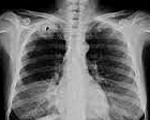

Рентгенография легких помогает выявить затемнение в области верхней борозды, утолщение плевры на верхушке легкого; часто обнаруживается деструкция I-III ребер, ниж­них шейных и верхних грудных позвонков. С помощью КТ или МРТ легких определяется степень инвазии опухоли в сосуды, лимфоузлы, ребра, позвонки, ткани грудной стенки. Эти сведения крайне важны для прогнозирования операбельности при раке Панкоста. Для оценки вовлеченности кровеносных сосудов возможно проведение артерио- или флебографии, либо контрастной компьютерной томографии.